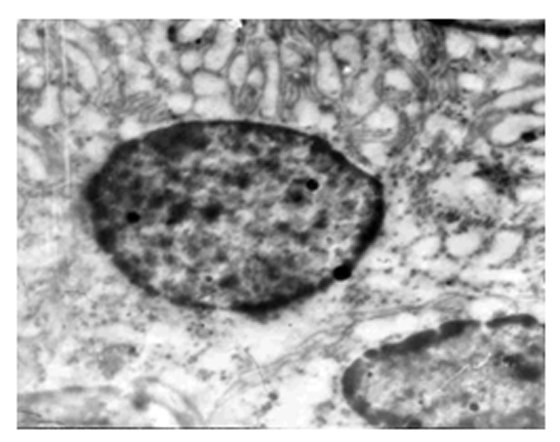

Полученные результаты указывают на то, что повышение уровня катехоламинов в крови при 2 ч компрессии мягких тканей находит свое отражение как на функции, так и на структурной целостности структурно-функциональной единицы почки. В период компрессии бедренной мышцы в течение 2 ч ультраструктурные изменения почки белых крыс имеют следующий характер: просвет капилляров расширен, наблюдается вакуолизация цитоплазмы эндотелия и ряд изменений в ультраструктуре органелл эпителиоцитов почечного тельца. Гладкий эндоплазматический ретикулум (ГЭР) представлен расширенными канальцами, имеет место вакуолизация цитоплазмы, а также маргинация гетерохроматина в ядрах (рис.1а,б).

Анализ полученных данных касательно повреждения клеточных структур нефрона почек 2 ч СДР и 4 ч декомпрессии–полнокровие ка-пилляров, транслокация эритроцитов через поврежденную эндотелиальную выстилку в субэндотелиальную зону, а также отек эпителия подоцитов, разрушение цитотрабекул, изменения в митохондриях, в гранулярном эндоплазматическом ретикулуме, расширение канальцев гладкого эндоплазматического ретикулума, вакуолизация цитоплазмы, наличие бесструктурных масс в просвете нефрона и маргинация гетерохроматина в ядрах, показал, что по характеру ультраструктурные изменения кровеносных капилляров и эпителиальных клеток напоминают картину гипоксии и рассматриваются как основные звенья в патогенезе СДР [2,7].